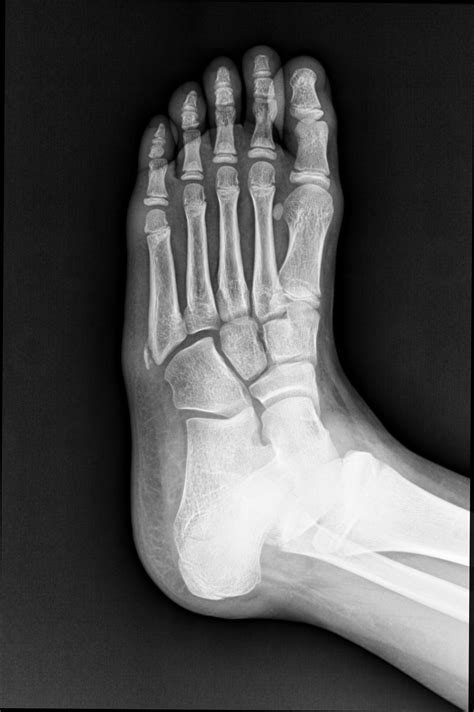

Diagnosing a Fifth Metatarsal Fracture

Diagnosing a Fifth Metatarsal Fracture typically involves a combination of physical examination and imaging tests. The diagnostic process may include:

• Physical Examination: A healthcare provider will examine the foot, checking for swelling, tenderness, and deformity.

• X-Rays: X-rays are the primary imaging tool used to confirm the presence and location of the fracture.

• CT Scans or MRIs: In some cases, more detailed imaging such as CT scans or MRIs may be required to assess the extent of the fracture and plan treatment.